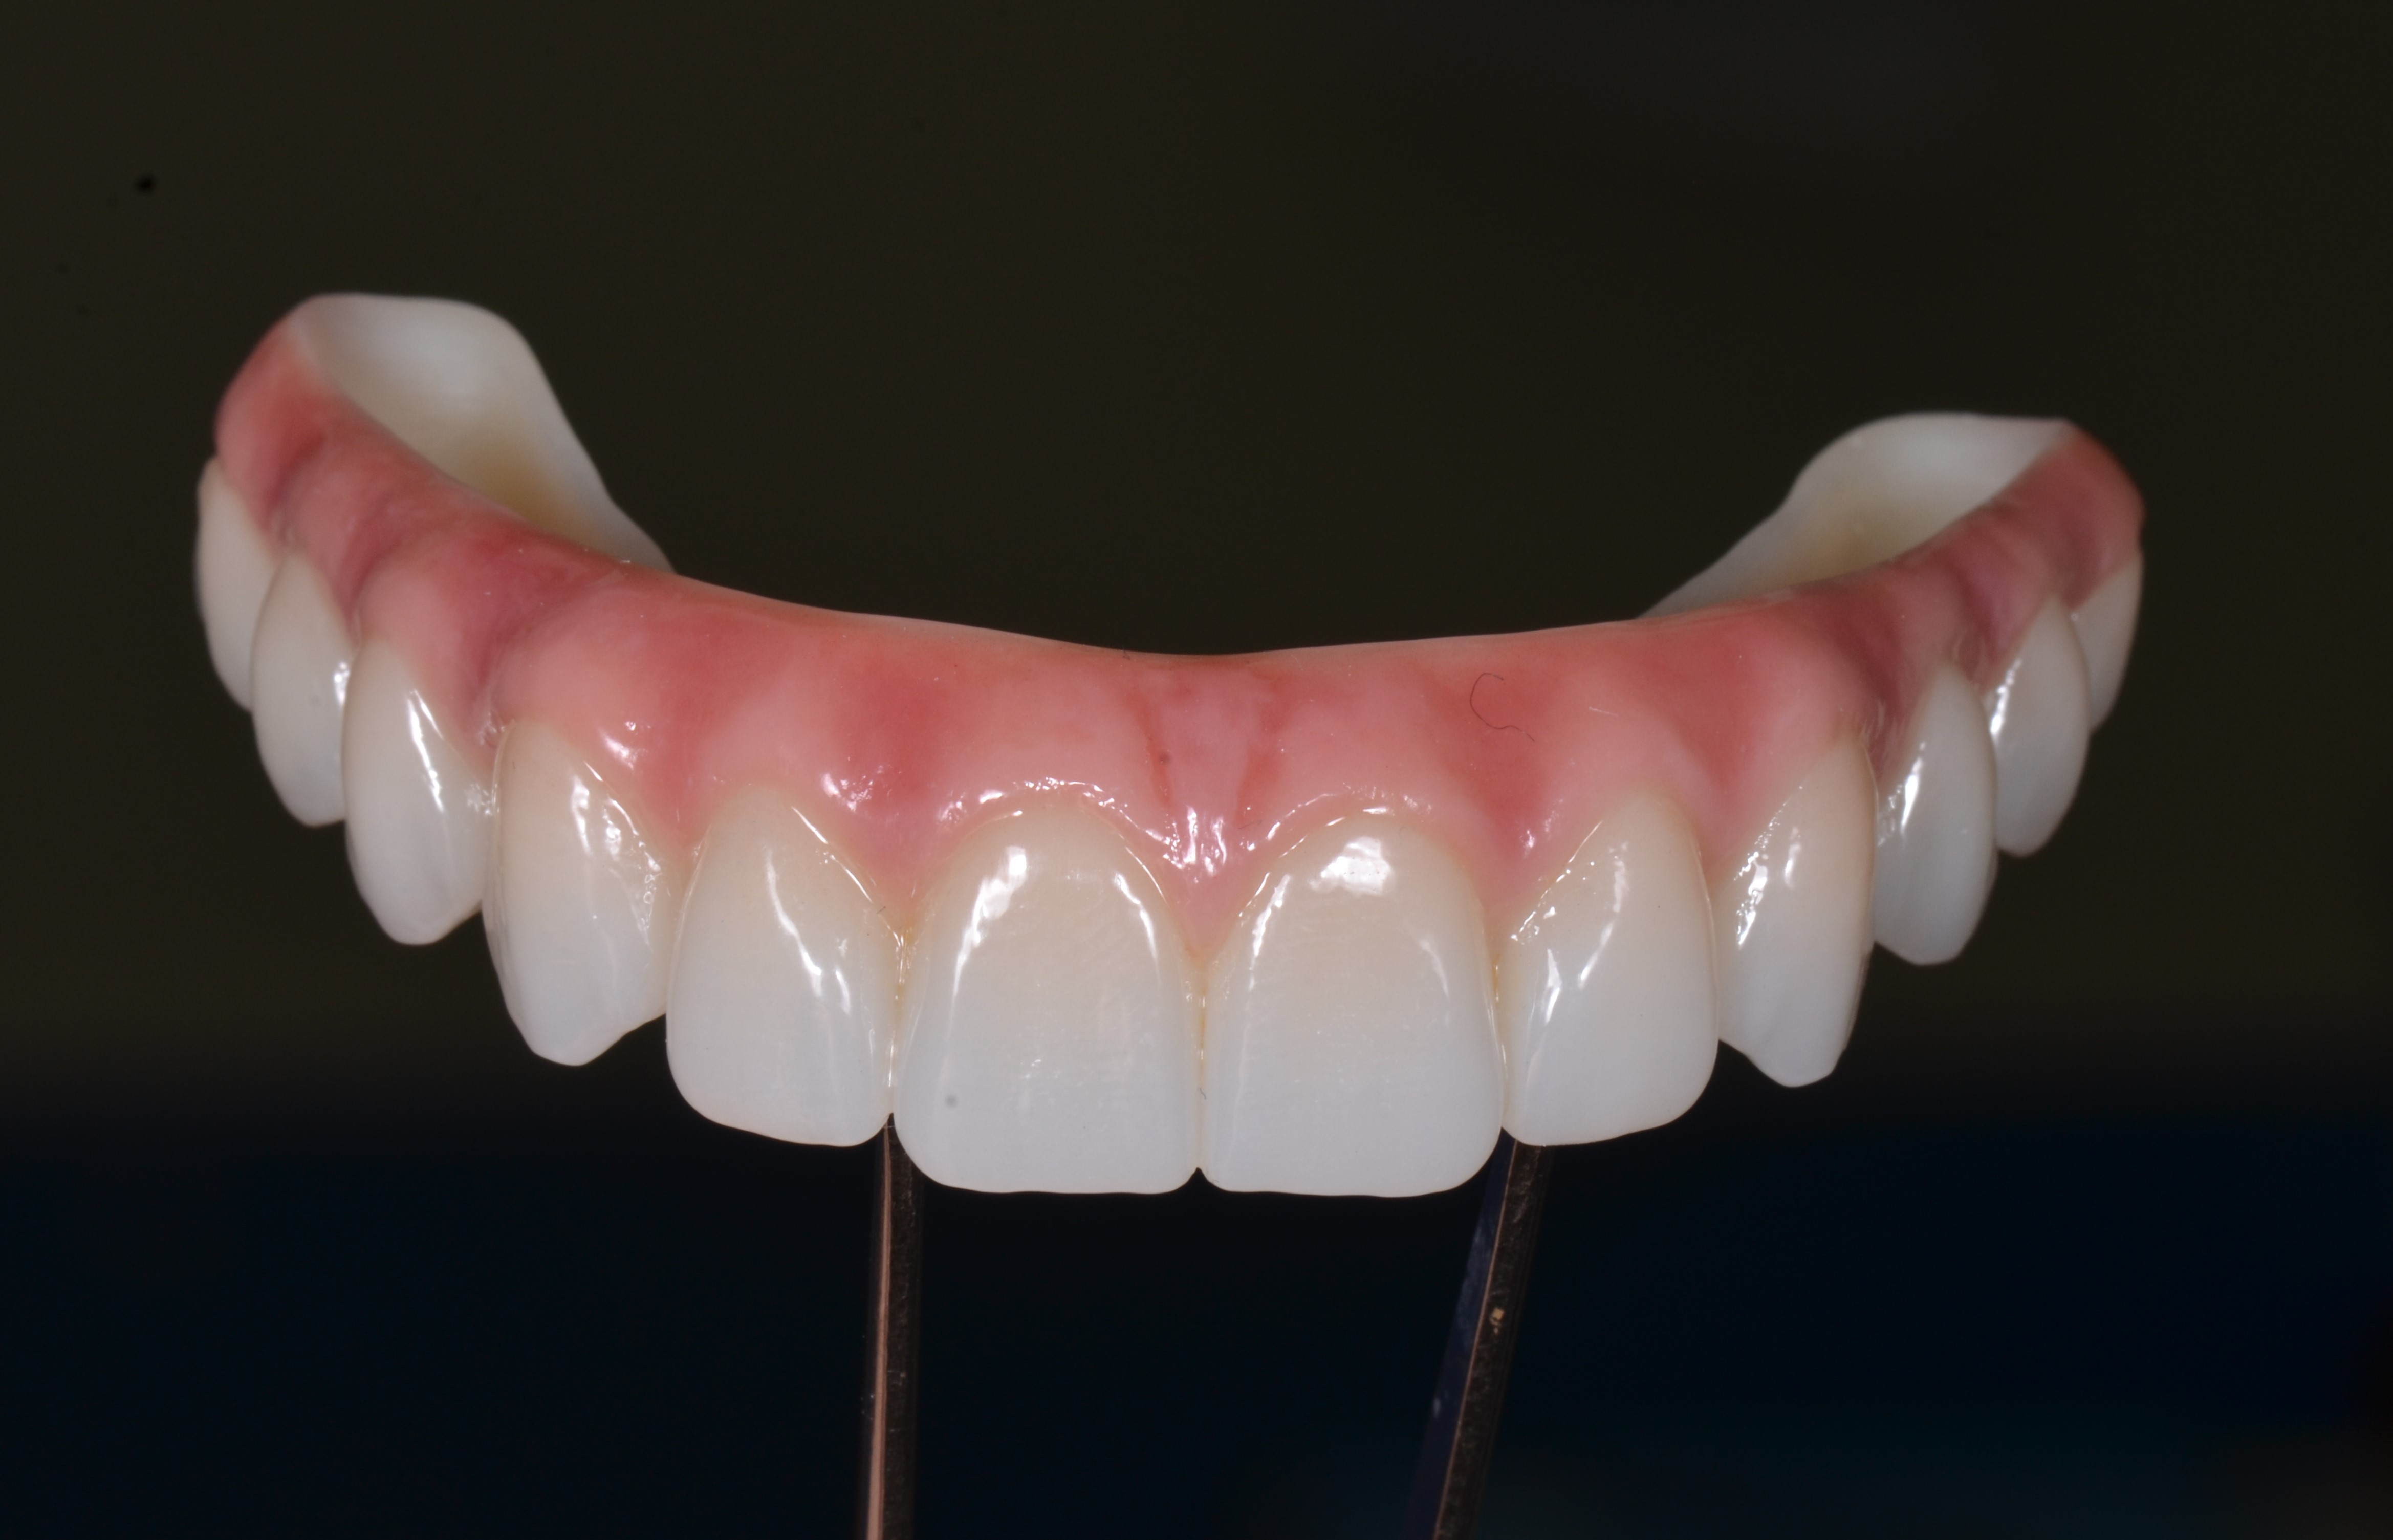

С эстетической и функциональной точки зрения провели диагностические оценочные манипуляции, согласовали с пациентом форму и цвет будущих зубов постоянной конструкции. Был изготовлен титановый фрезерованный каркас с индивидуальными абатментами NobelProcera® (рис. 44), с последующим изготовлением коронок из Диоксид циркония и имитацией розовой десны (рис. 45).

Через 8 месяцев после имплантации была зафиксирована несъёмная мостовидная керамическая конструкция с титановым каркасом по методике «All – on – 4» (рис. 46).